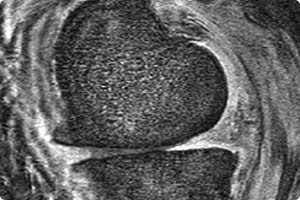

bedeutendsten Volkskrankheiten unserer Zeit. Sie geht mit einer Zerstörung des Gelenkknorpels einher und kann prinzipiell jedes Gelenk betreffen, jedoch sind das Knie und Hüftgelenk am häufigsten betroffen, gefolgt vom oberen Sprunggelenk, Schulter, Ellenbogen und Hand. Es ist eine Erkrankung, die mit schmerzhaften Einschränkungen der Gelenkbeweglichkeit einhergeht und letztlich zu einem Verlust der Selbstständigkeit führt.